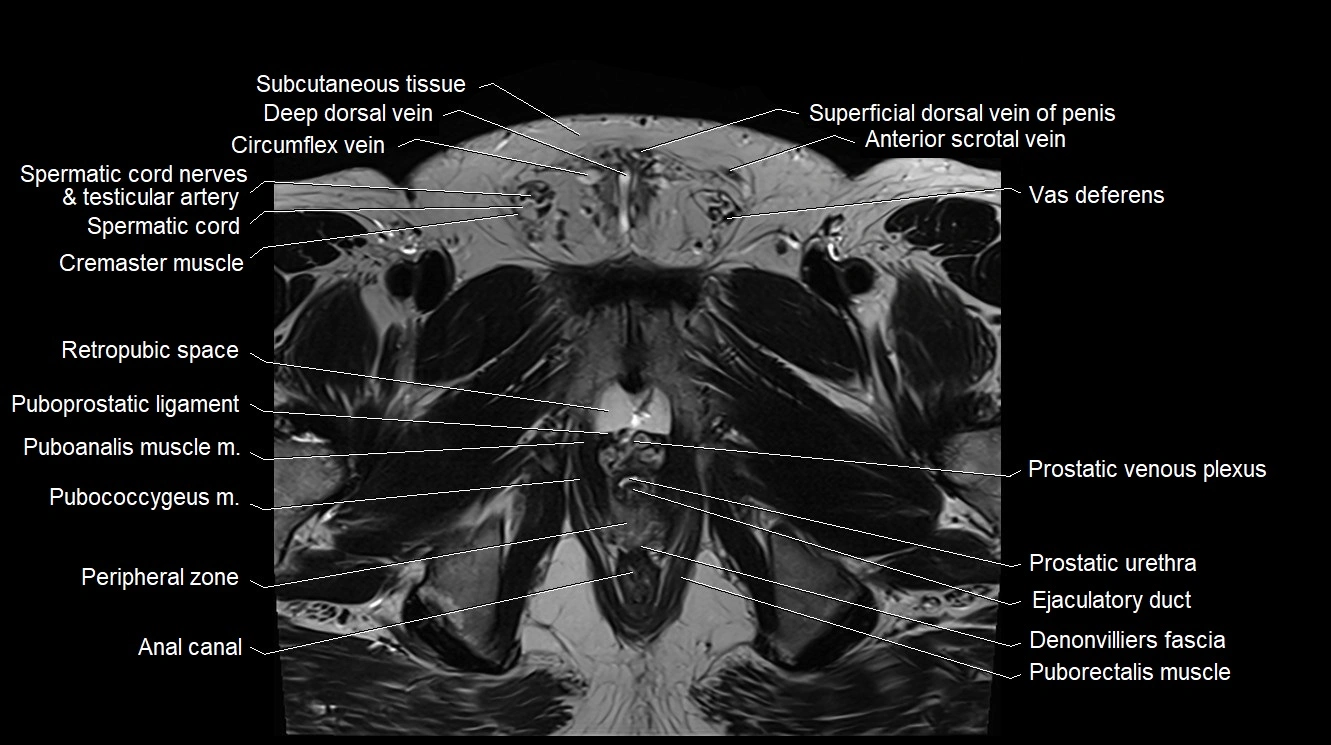

MRI image